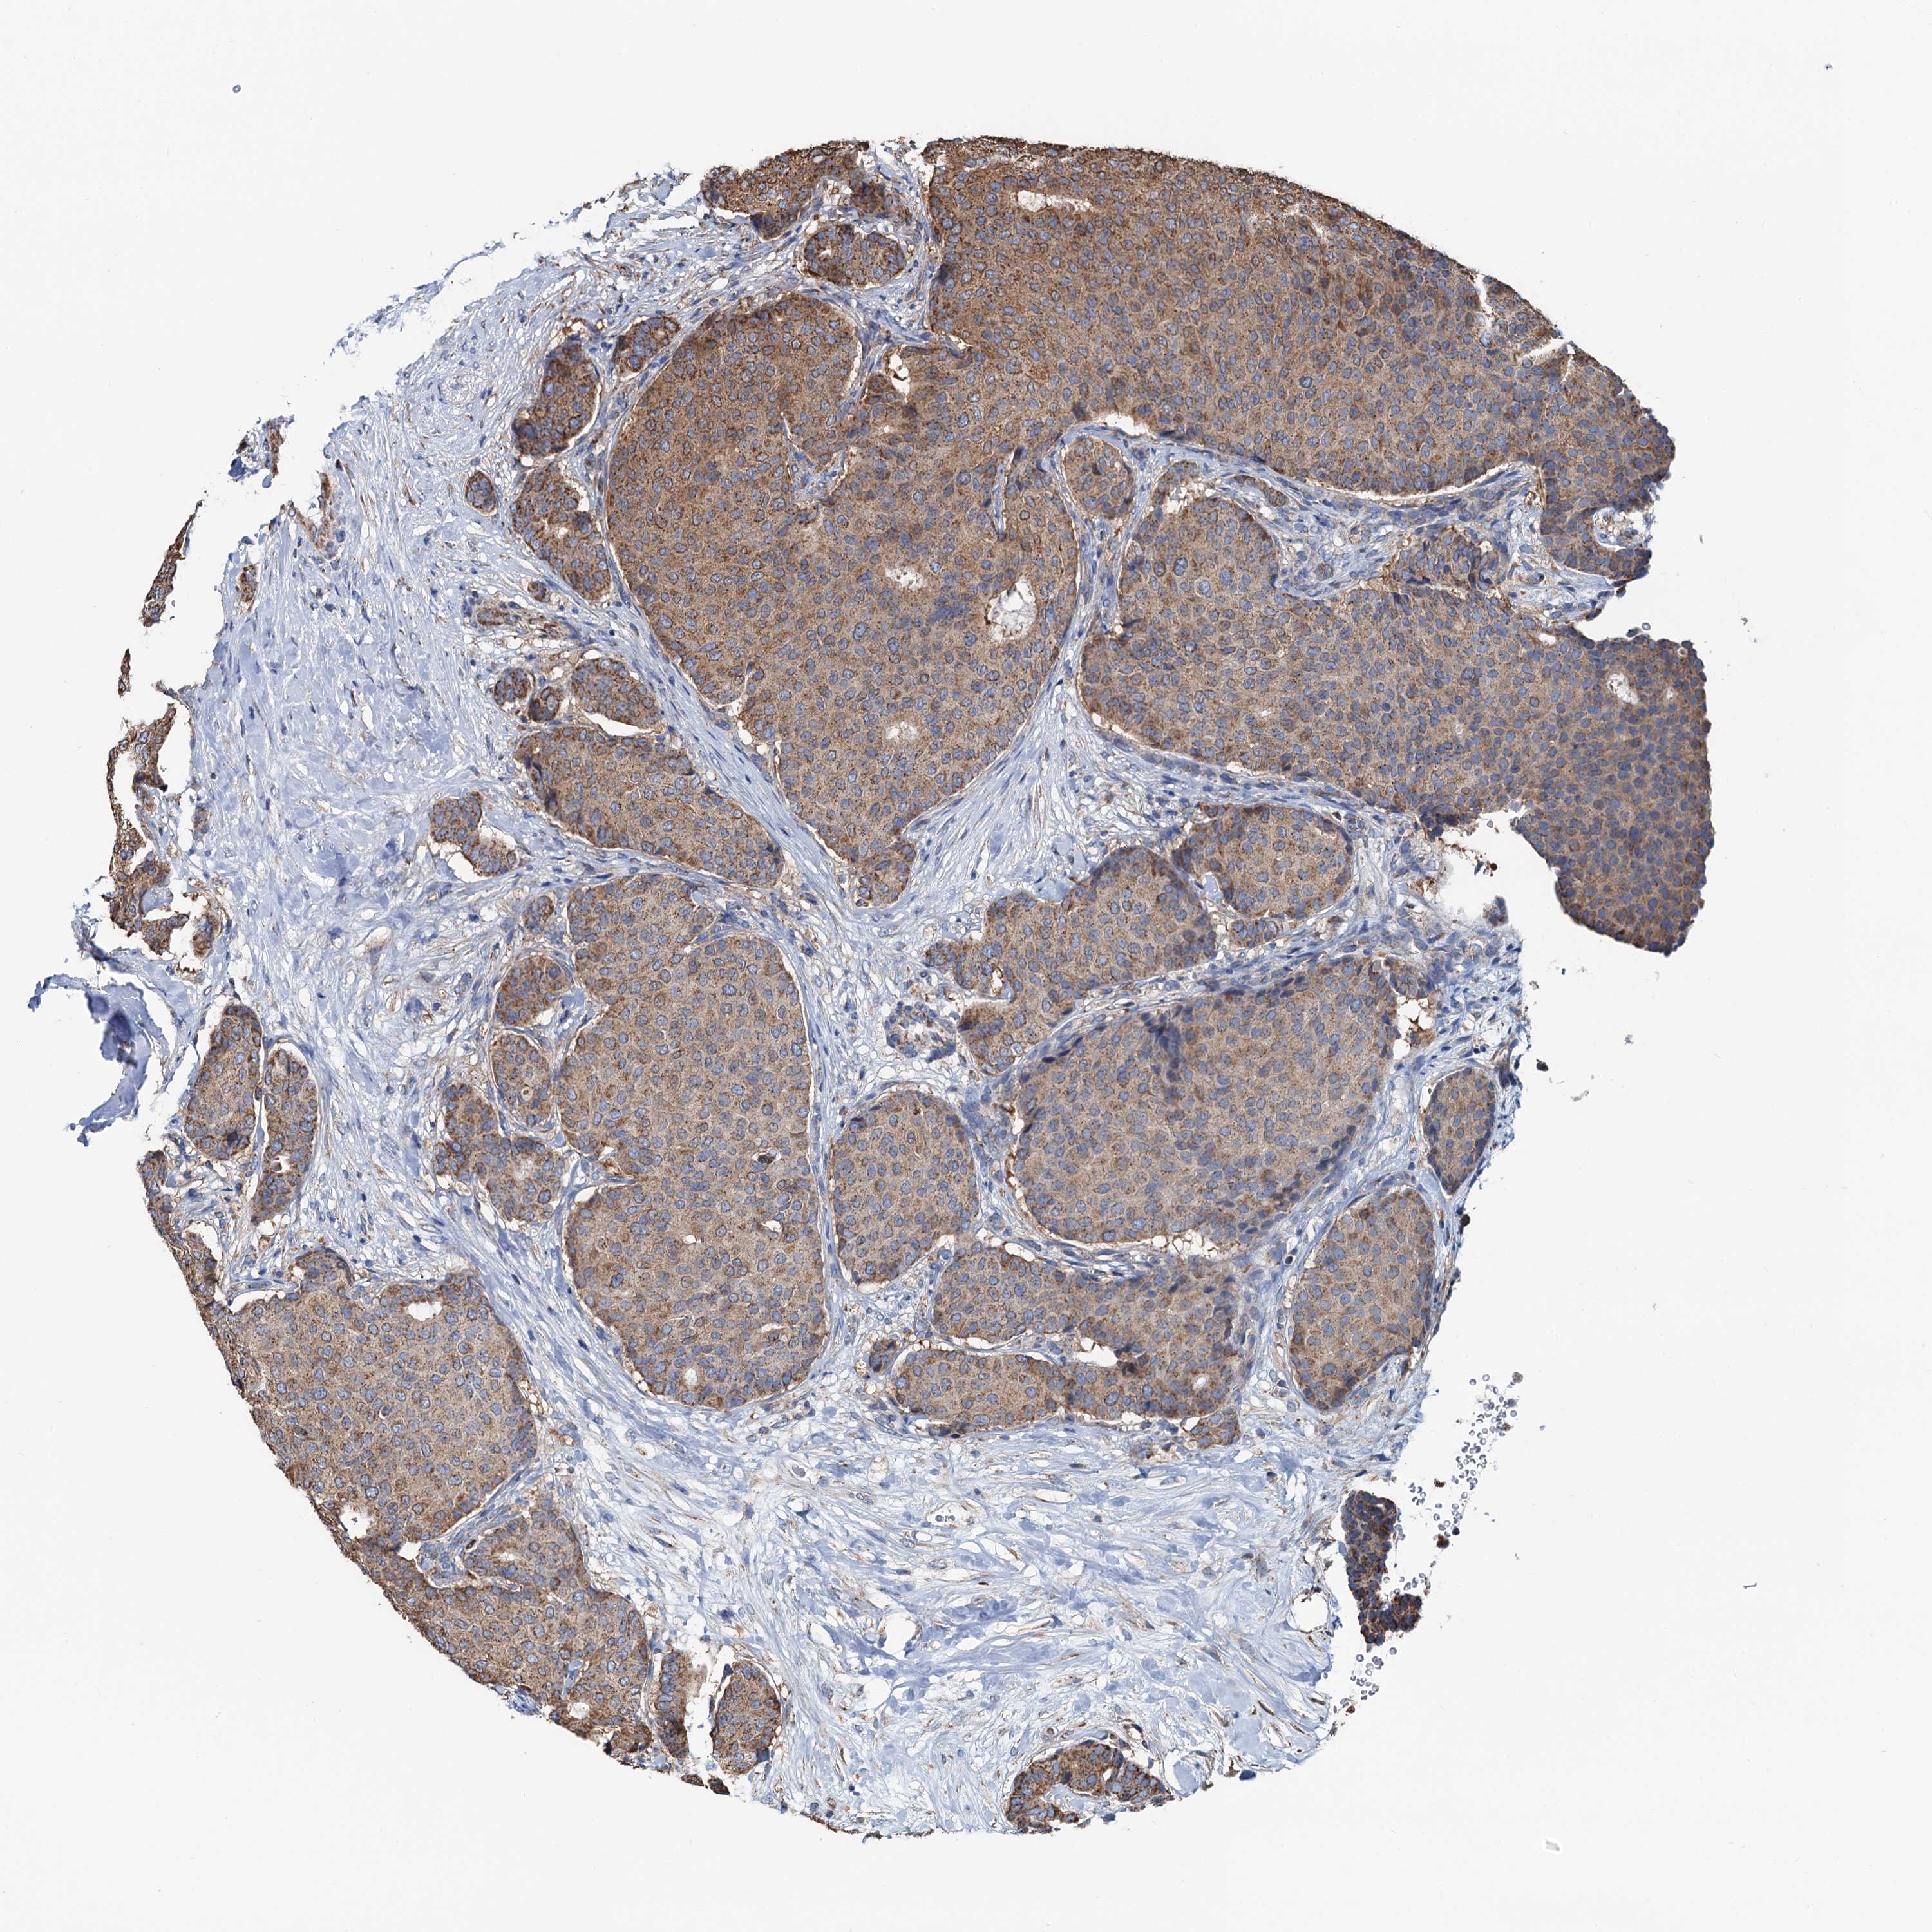

CANCER BREAST CANCER Show tissue menu

BRCA TCGA BRCA VALIDATION PROTEIN EXPRESSION